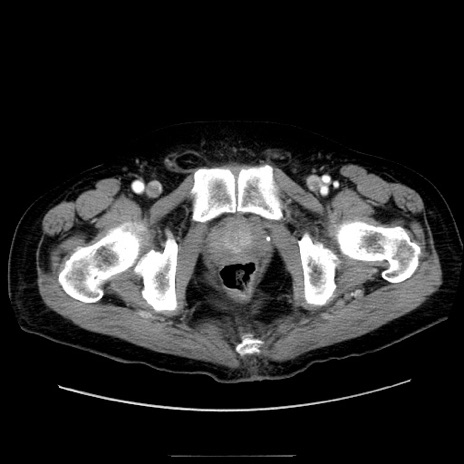

冠状断像

症例30(横断像)

【症例】80歳代男性

【主訴】臍周囲痛

【現病歴】約6時間前から臍下部痛が出現。次第に腹部膨隆・背部痛も生じてきたため来院。背部痛の場所は変化しない。

【既往歴】腎盂腎炎

【身体所見】意識清明、BT 36.3℃、BP  131/87mmHg、P 87bpm、SpO2 100%(RA)、臍周囲自発痛・圧痛あり、反跳痛なし、自発痛部位に一致して板状硬あり、腹部膨隆、腸雑音減弱、CVA tenderness両側陰性。

【データ】WBC 19600、CRP 0.33